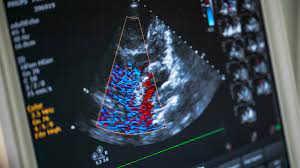

The next morning in the ICU they came to take me to run a test called an Echocardiogram which checks how the hearts chambers and valves are pumping blood through my heart. It also checks for any damage to the heart muscle or if there was any pericardial effusion. After running the test and returning back to my room, the Doc told me that I was able to leave the Hospital that day! I was stunned! He told me that the procedure was a complete success and that there was no damage to my heart and that I was clear of any blockage!! I was shaking and in disbelief! I had questions. Several questions, about future diet, exercise habits and medicines. As I was firing them off, one by one, I realized that most of my questions are the very same ones we asked my Father’s doctor, 42 years ago. He addressed all of my concerns about everything. He gave me the recipe to live another 30 years!